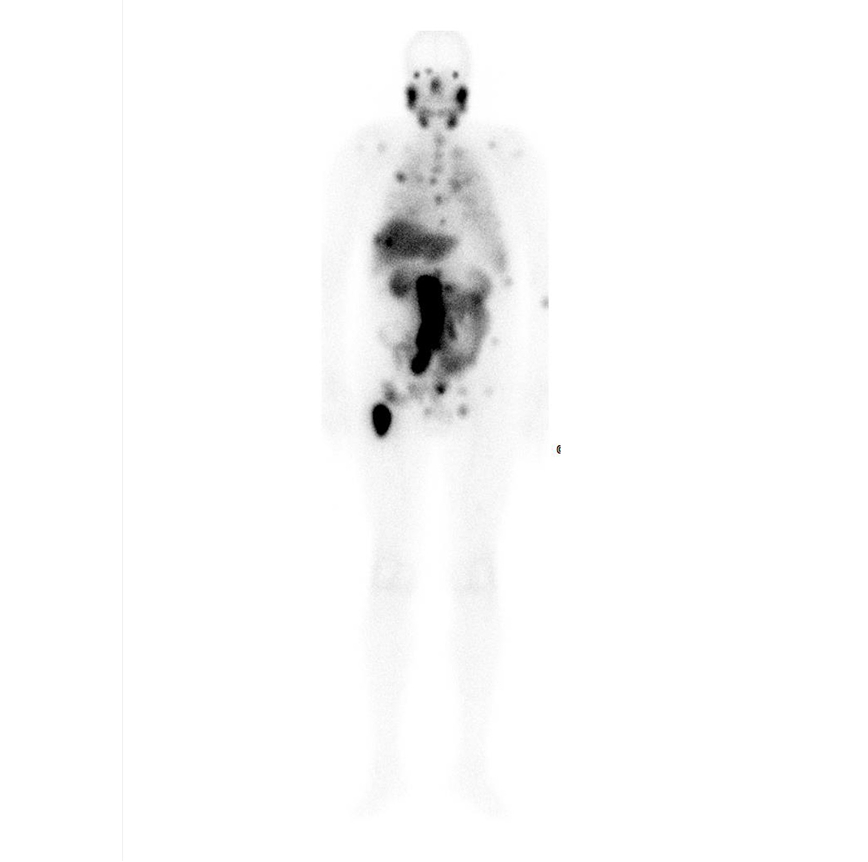

Caso condiviso da Saima Mushtaq

Paziente con anamnesi di malattia coronarica e pregresso impianto di stent sulla discendente anteriore sinistra.